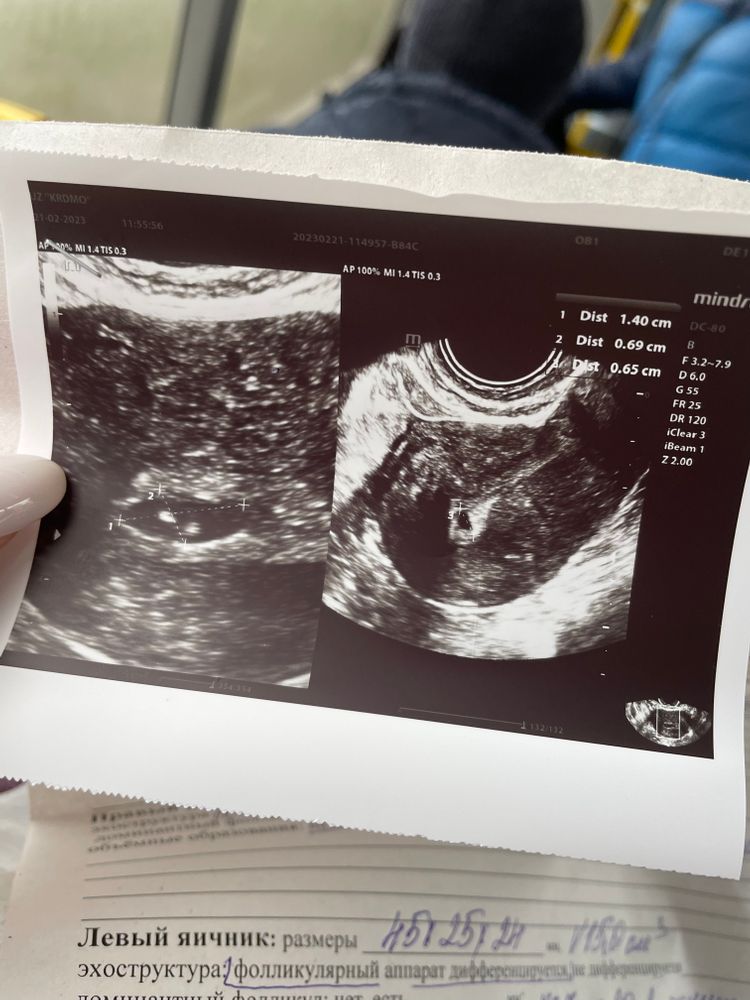

На УЗИ уже давно можно сходить, особенно при таких болях. Даже одна неделя даёт хорошую динамику. Две недели это они прям перегнули с такими симптомами. Неправильной формы пя может быть и из-за того, что организм пытается его отторгнуть, но также и от тонуса.

Irsa, дюфастон так же назначают , чтобы вызвать месячные. может поэтому такой эффект. Не знаю . По поводу сохранения-сказала похоже на замершую или неразв. Беременность так как не видно эмбриона